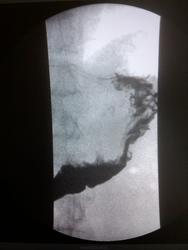

Пациент, 60 лет. На ФГДС: В антральном отделе отмечается некоторая ригидность на малой кривизне, рядом с привратником.

Не вижу изменений в антральном отделе, но обращает внимание некоторая ригидность задне-медиальной стенки субкардиально.

Обратила внимание на уплощение контура на малой кривизне препилорического отдела. Но только на одном снимке, на остальных - без особенностей. Вряд ли стоит придавать этому значение. Вы видели моторику - Вам судить